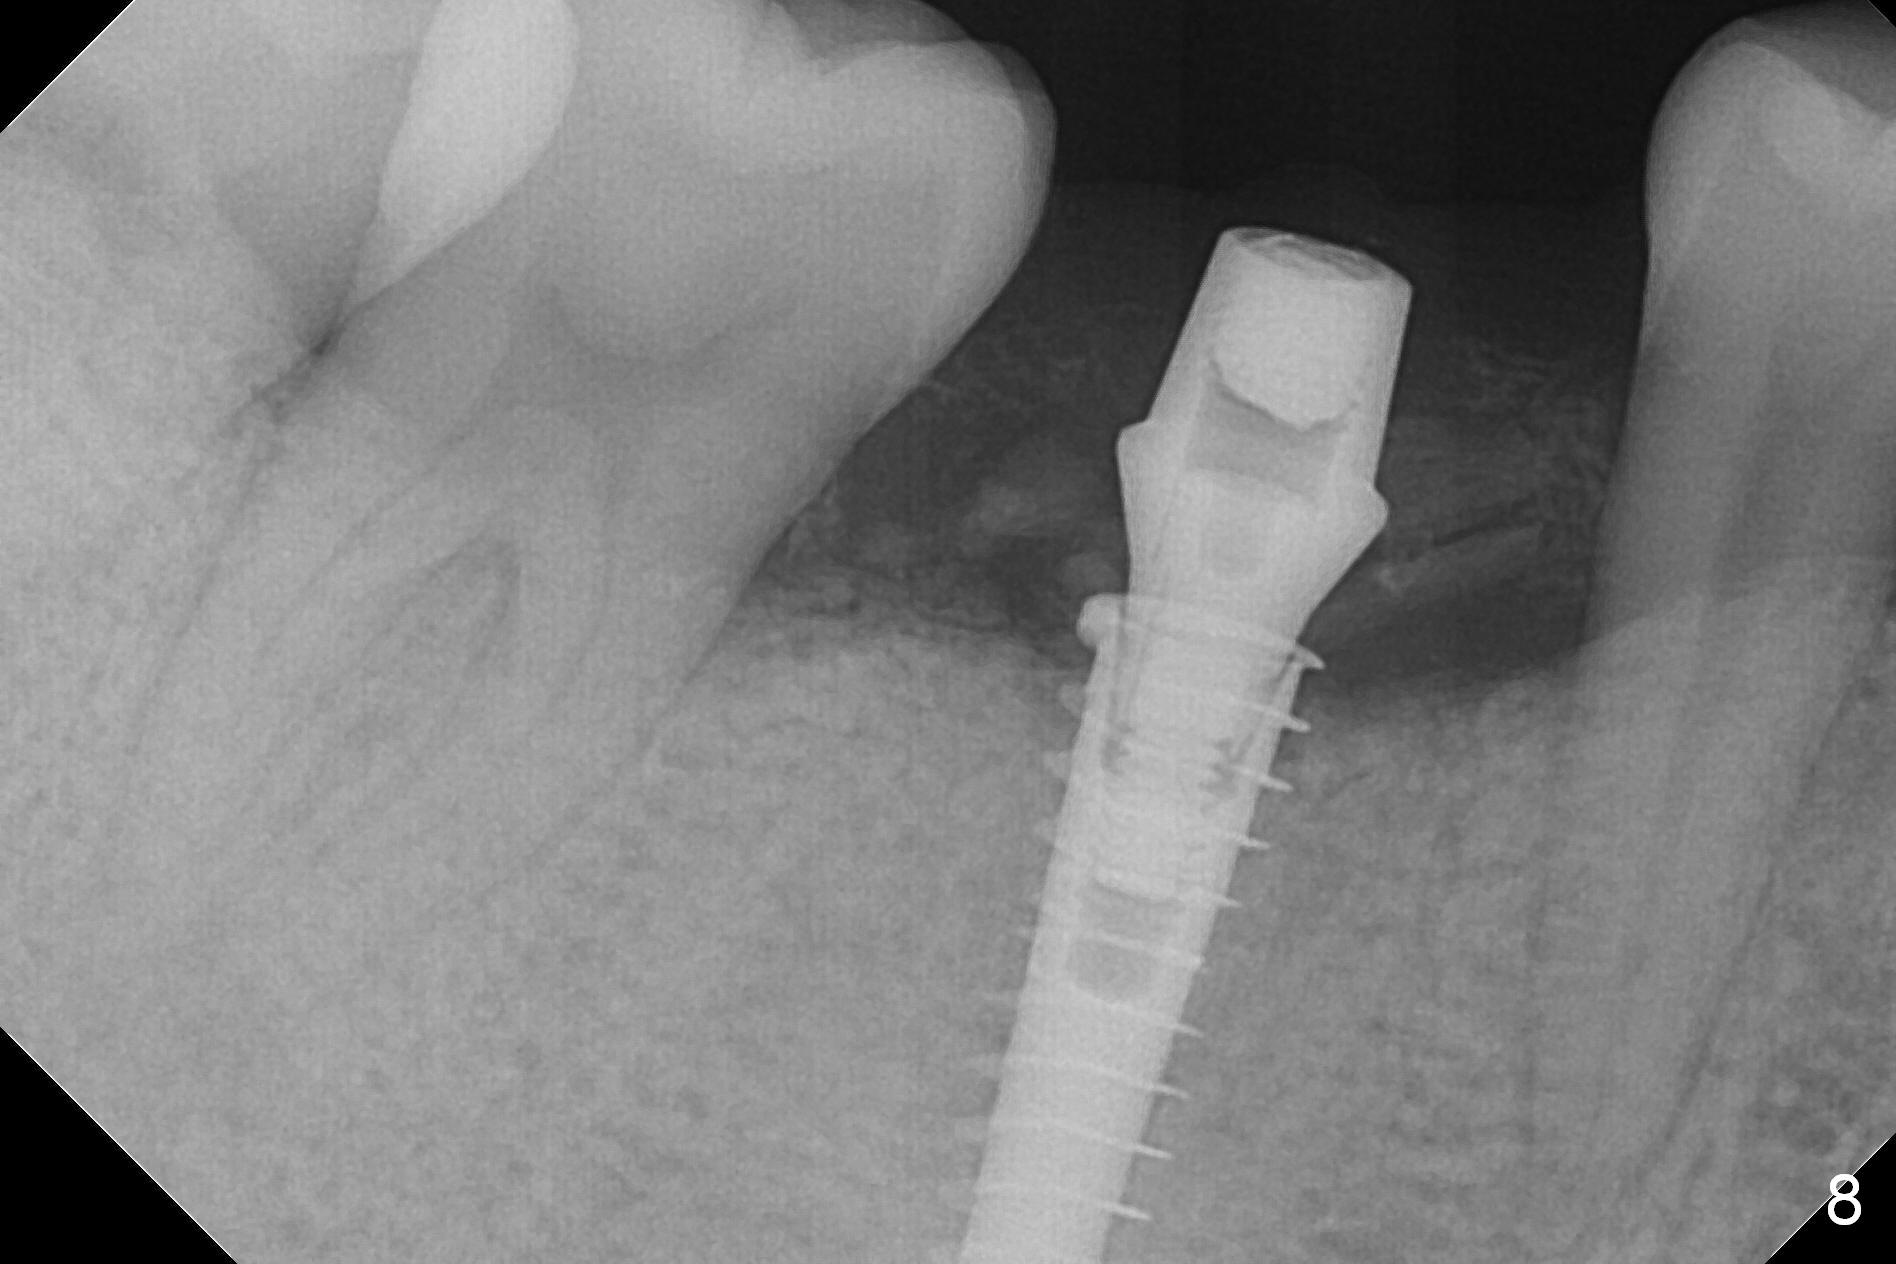

The patient returns 5.5 months postop for final restoration. The implant appears to have osteointegrated (Fig.8). When the locked in provisional is removed, the gingiva bleeds (Fig.9). She will return in 2 weeks. The abutment remains incompletely seated nearly 2 years post cementation (Fig.10).